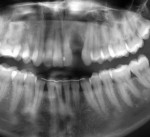

Sinus Lift With Simultaneous Implant